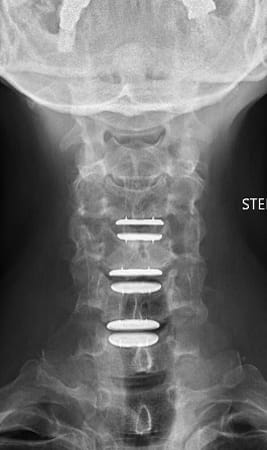

Auf diese Weise wird die Belastung der Wirbelsäule wie bei einer natürlichen Bandscheibe aufgenommen. Bei chronischen Bandscheibenerkrankungen sollte zuvor eine mindestens 3-monatige konservative Therapie versucht werden. Ist diese erfolglos oder treten nicht beherrschbare Schmerzen oder Nervenstörungen auf, so übernehmen die Krankenkassen in der Schweiz die Operation, sofern nicht mehr als zwei Bandscheiben betroffen sind und keine primäre Arthrose der Facettengelenke vorliegen. Bei akuten Bandscheibenvorfällen mit schweren Nervenstörungen oder Lähmungen besteht ebenfalls die Indikation zur Operation. Diese wird von vorne durch einen kleinen, etwa 2-3 cm langen, queren Hautschnitt in einer Hautfalte am Hals vorgenommen. Rechts oder links seitlich der Luft- und Speiseröhre gelangt man sehr schonend auf die Halswirbelsäule. Auf diese Weise kann die betroffene Bandscheibe vollständig entfernt werden und der Rückenmarkskanal sowie die entsprechenden Nervenwurzeln entlastet werden. Anschließend wird der Bandscheibenraum mit speziellen Instrumenten auf seine normale Höhe aufgedehnt, um die Nervenwurzeln zu dekomprimieren und Platz für die Prothese zu schaffen. Nach Ausmessen der passenden Größe und präziser Vorbereitung des Implantatbettes wird das Implantat unter Röntgenkontrolle eingesetzt. Beispiel einer degenerativen Bandscheibenerkrankung an der HWS und Versorgung mit drei visko-elastischen Bandscheibenprothesen

nach OP seitlich